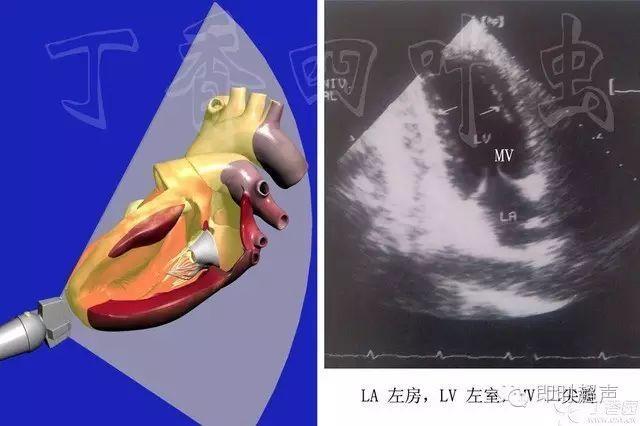

五腔心切面,心尖五腔心切面示意图

二维超声心动图基本切面: 心尖四腔心切面

图文详解 | 心超切面不会打?看这一篇就够了!

心尖五腔心切面示意图

五腔心示意图

心脏超声切面

四腔心切面